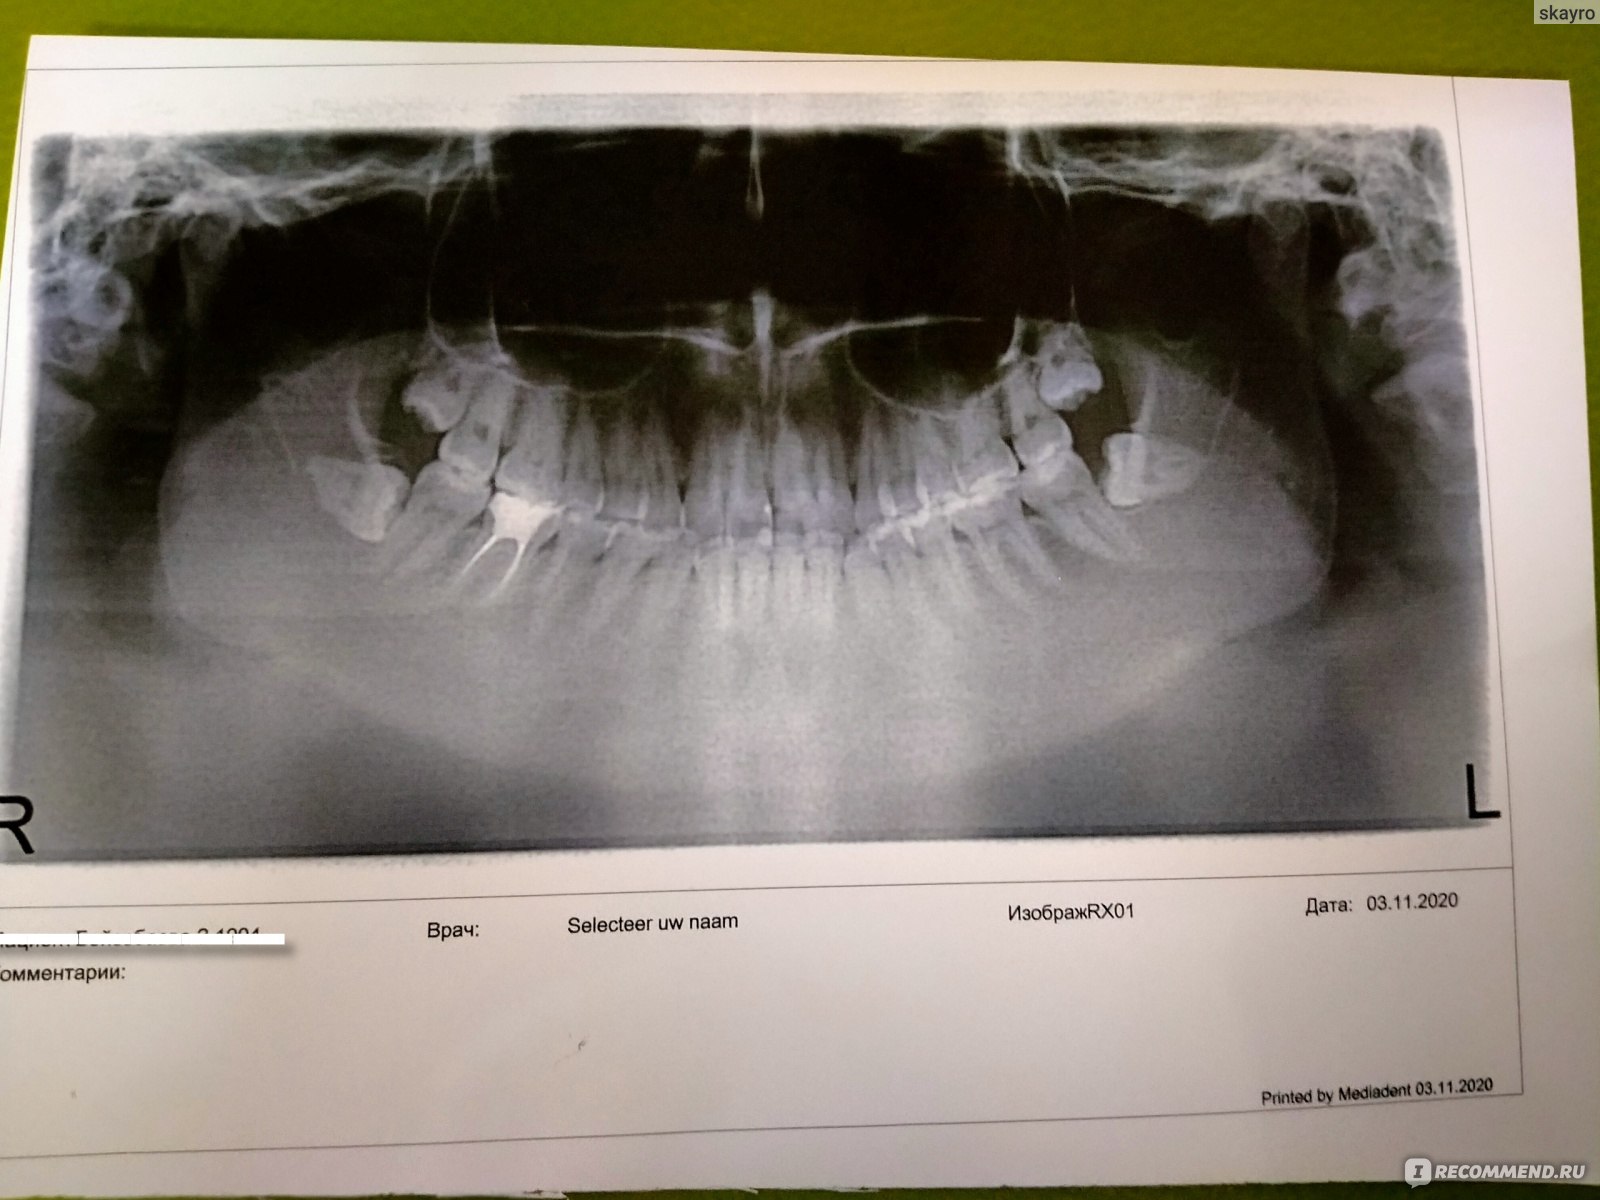

Рентгенография небного шва: Медицинские исследования и диагностика